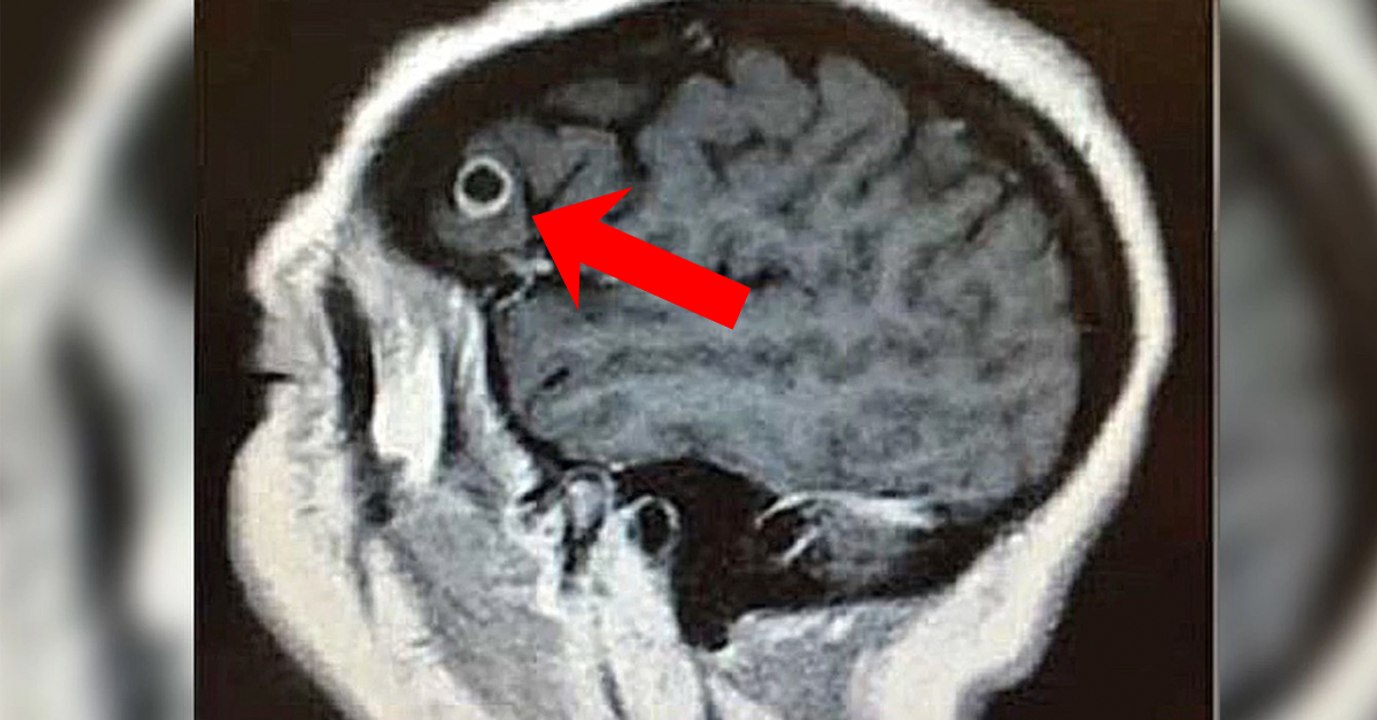

Bei der OP merken die Ärzte: Der Gehirntumor dieser Frau ist etwas ganz anderes